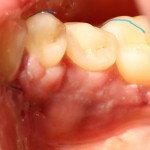

А вот фотография через месяц после операции:

Задайтесь вопросом — оно того стоило? 30 минут в операционной, 4 дня на реабилитацию и 2 недели со швами? Стоило ли это того, чтобы в будущем избежать серьезных проблем со здоровьем?

На мой взгляд — да.